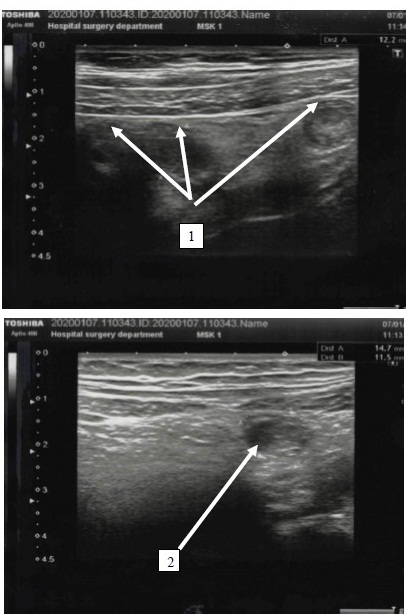

The results of the study. The ultrasound signs of acute appendicitis included the presence of a blindly ending tubular structure at the point of maximum pain with an outer diameter of more than 6 mm, which cannot be compressed, aperistalsis, wall thickness more than 2 mm, and the presence of coprolite in the lumen of the tubular structure (fig. 1). In transverse scanning, the tubular structure was in the form of a «target», «cockade»; the thickness of the stromal component of the wall of the appendix was more than 1.5 mm (fig. 2).

Fig. 1. An echogram of the vermiform appendix: 1 – a tubular formation with thickened walls, with a «double contour» is visualized; 2 – in the lumen of the tubular structure, fluid and dense masses